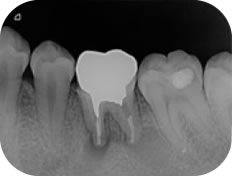

再根管治療

再根管治療は、過去に根管治療を行った歯に、再度根管治療を行うことをいいます。

過去の根管治療の際に、細菌の感染に対する処置が不十分であったり、虫歯が原因で根管が感染し根尖性歯周炎が再発した場合などに行われる治療です。

再根管治療の成功率は40%~80%といわれており、それまでの根の治療の質によって大きく左右されます。

再根管治療では、前回の治療でどのような処置が行われたか、正確に診断することが大切です。

髙橋歯科では、かかりつけの医院様と密な情報交換を行い、患者様がこれまでにどのような治療をおこなってきたかなどをしっかりと把握したうえで治療をすすめてまいります。

また、再治療の場合は、初めての根管治療に比べて歯根破折などを起こす可能性があるため、より慎重かつ正確に治療をすすめることが重要です。

そのため髙橋歯科では、マイクロスコープとよばれる歯科用の顕微鏡を用いて治療を行っております。

また、無菌環境下で治療を行うことで、細菌の感染を防ぐことにも細心の注意をはらっております。